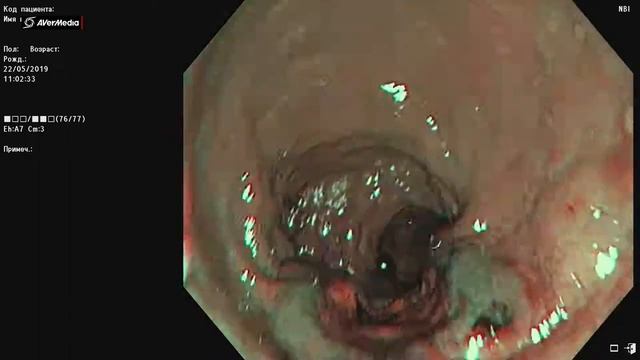

В «СМ-Клиника» эндоскопические исследования (и диагностические, и оперативные) могут проводиться в комфортных условиях седации. ⠀

Многие люди откладывают поход к специалисту по эндоскопии из-за боязни введения внутрь эндоскопа. Седация поможет решить эту проблему и без страха и дискомфорта пройти этот метод объективной диагностики и эффективного лечения.⠀